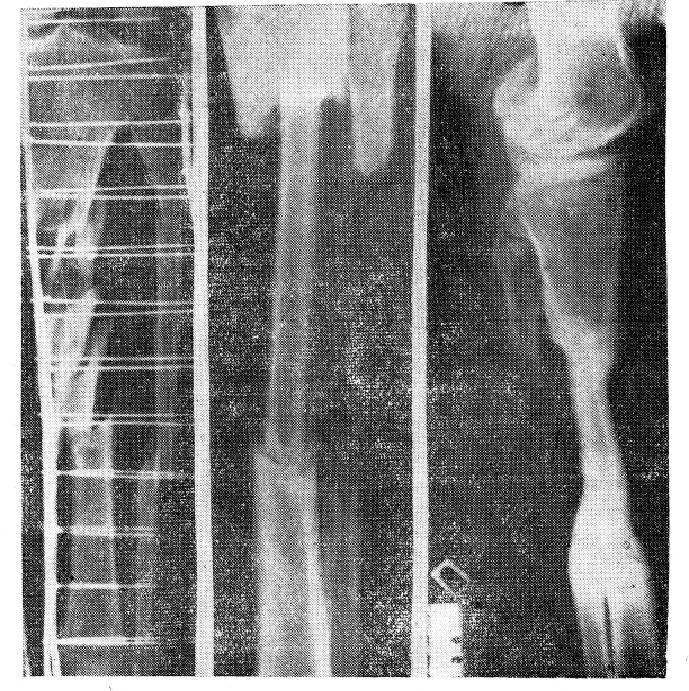

На рентгенограмме от 9/ІХ 1958 г. определяется крупнооскольчатый, сегментарного типа перелом верхней и средней трети большеберцовой кости. На этом же уровне соответственно краям нижнего и верхнего отломков большеберцовой кости определяется двойной перелом малоберцовой кости. При этом длина среднего, промежуточного отломка несколько больше заполненного костными отломками дефекта большеберцовой кости (рис. 1 — а).

Рис.1 Рентгенограммы голени. Объяснения в тексте.

После выведения больного из шока, через 7 часов после травмы, под ингаляционным наркозом произведены пробная лапаротомия и хирургическая обработка раны правой голени с перемещением малоберцовой кости. Края раны частично иссечены. Удалены размозженные мышечные ткани длинного разгибателя пальцев и передней большеберцовой мышцы. При обследовании костных отломков оказалось, что последние сильно загрязнены и не связаны с надкостницей. При удалении их образовался дефект большеберцовой кости длиной до И—12 см. Учитывая, что в дальнейшем возникнет необходимость замещения этого дефекта, во время операции принято решение использовать видимую в ране малоберцовую кость. Это было тем более целесообразно, что уровень переломов малоберцовой кости соответствовал уровню дефекта большеберцовой. Окруженный сохранившимися мышцами промежуточный отломок малоберцовой кости вместе с ними был перемещен медиально и после освежения концов плотно внедрен в костномозговые каналы центрального и периферического отломков большеберцовой кости (рис. 1 — б). Рана зашита редкими кетгутовыми швами с введением для дренажа двух резиновых полосок. На некоторых участках кожи для оттока раневого секрета и уменьшения натяжения в шахматном порядке сделаны насечки. Конечность фиксирована циркулярной гипсовой повязкой с окном на месте раны.

Для осмотра прибыл через 2,5 года после травмы. Ось правой нижней конечности правильная; деформация незначительная; укорочение голени — 2,5 см. Ходит без тутора, полностью нагружая ногу и пользуясь палочкой. На рентгенограмме от 3/11 1961 г. определяется гипертрофия прочно сросшегося трансплантата малоберцовой кости с центральным и периферическим отломками большеберцовой кости, с некоторым угловым расположением в области бывшего дефекта. Между периферическим концом трансплантата и дистальным фрагментом малоберцовой кости образовался мощный костный мостик (рис. 1 —в).